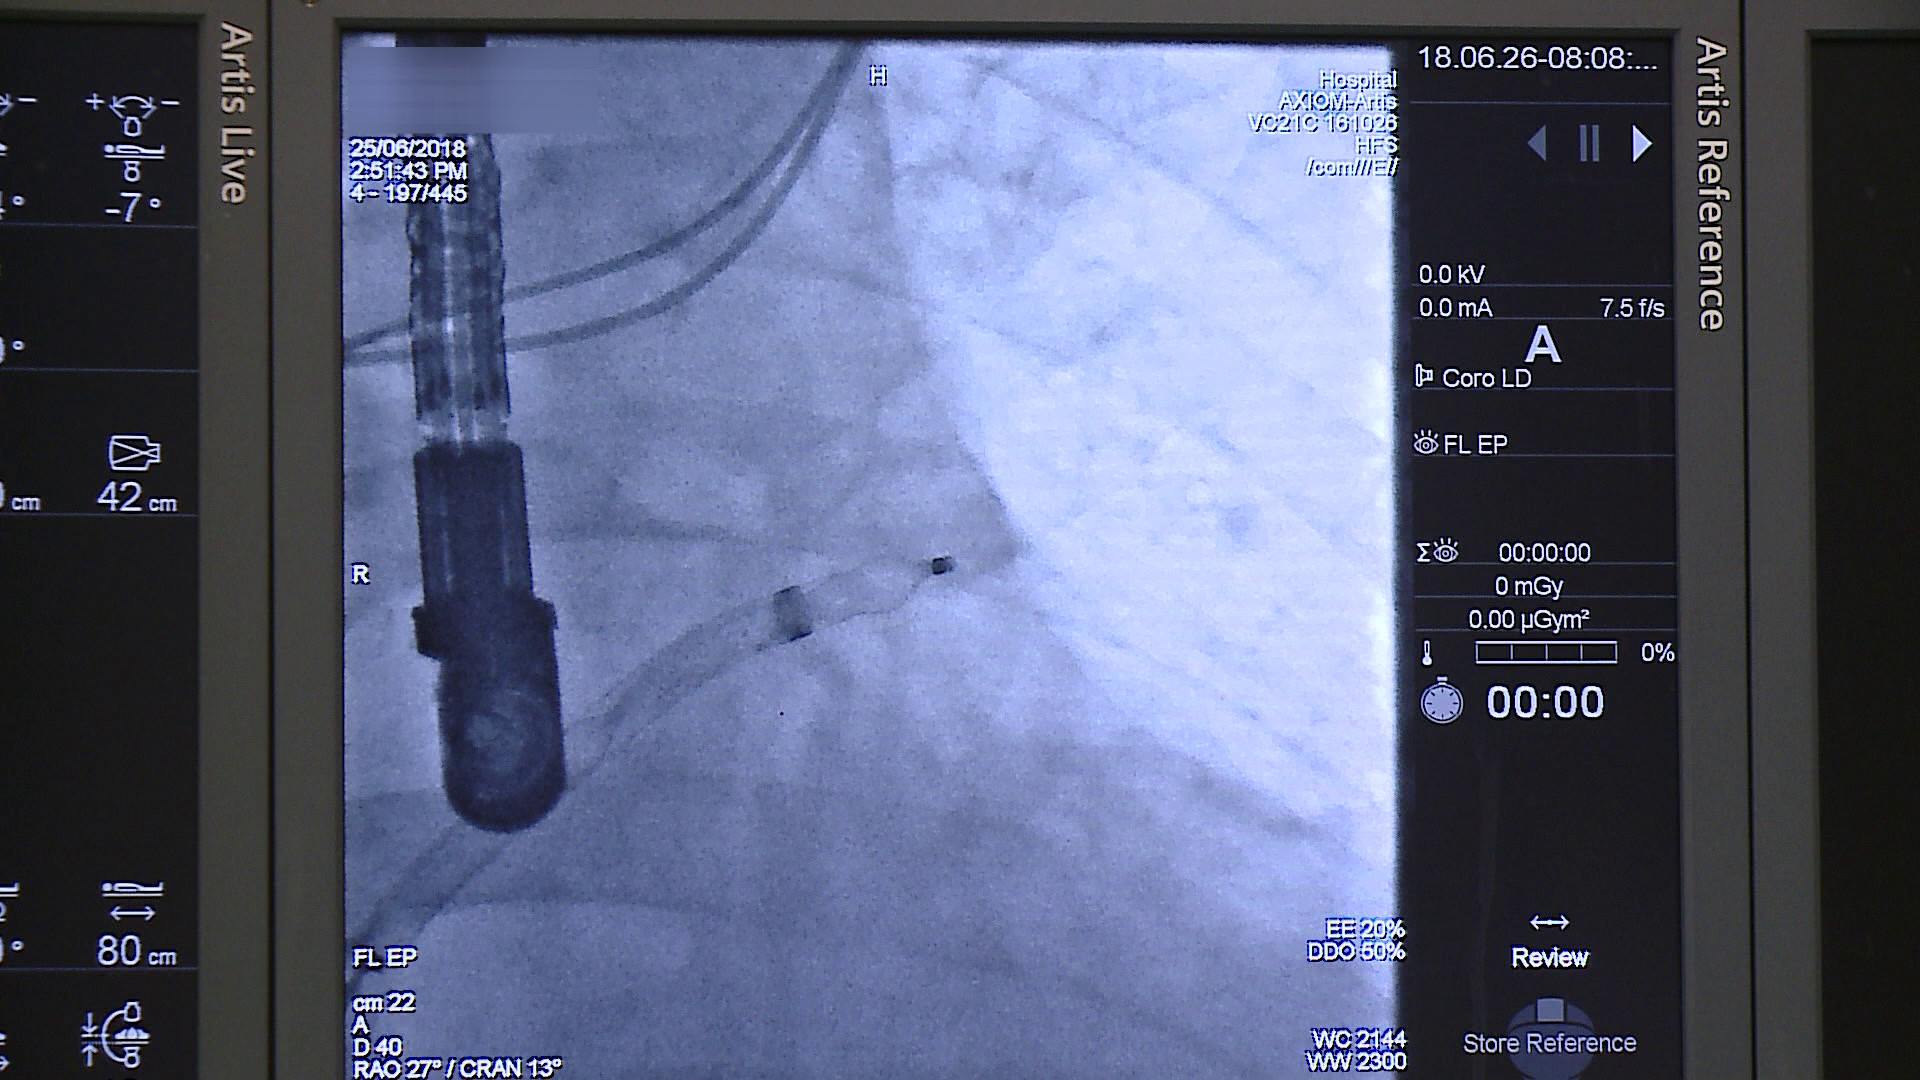

Zabieg polega na wprowadzeniu przez żyłę w pachwinie specjalnego okludera i umieszczeniu go w lewym przedsionku serca. Zabieg jest wykonywany w znieczuleniu płytkim ogólnym i trwa około godziny. Dzięki temu pacjent nie musi być hospitalizowany przez kilka dni.

Pierwsi trzej pacjenci zostali zoperowani w poniedziałek (25 czerwca) pod okiem profesorów ze Śląskiego Centrum Chorób Serca w Zabrzu.